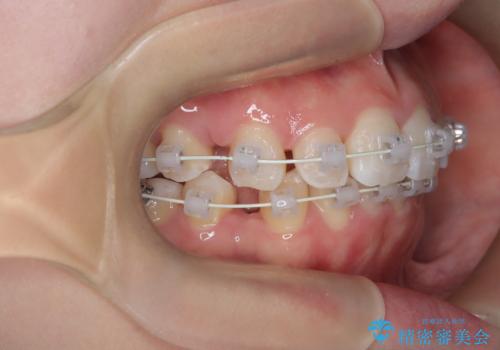

- 「歯のでこぼこと捻じれを治したい」を主訴に来院された患者様です。矯正検査の結果、上顎前歯がかなり唇側傾斜という結果になったので上下左右4番を抜歯をしワイヤー矯正で治療を行いました。

抜歯矯正でしたが順調に治療が進み2年で矯正治療を終えることが出来ました。歯のでこぼこや捻じれが治り、口元も下がって患者さんも大変満足されていました。